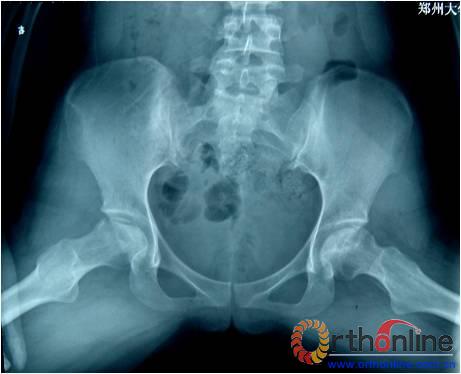

图为:方某,女,21岁,双侧激素性股骨头坏死,ARCO III-C期,C.F.P. 股骨假体THA前后双髋X线摄片。

图1、图2:术前;图3:术后;图4:术后3个月;图5:术后6个月;图6:术后1.2年